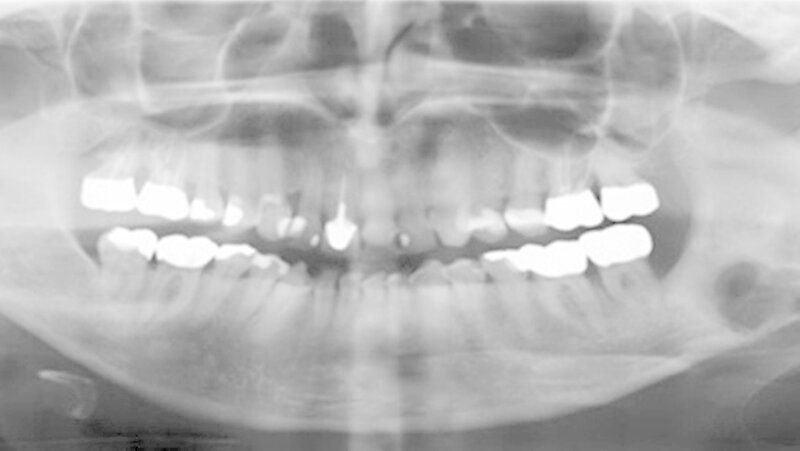

Der Heilungsverlauf gestaltete sich ohne Einschränkung der fazialen Sensomotorik stadiengerecht. Im Anschluss wurde ein Orthopanthomogramm (OPT) als postoperativer Kontroll- und Ausgangsbefund angefertigt (Abbildung 5). Es erfolgte eine klinische und röntgenologische Nachkontrolle drei und sechs Monate post operationem. Hierbei zeigte sich eine regelrechte Reossifizierung der Defektregion im Kieferwinkel.